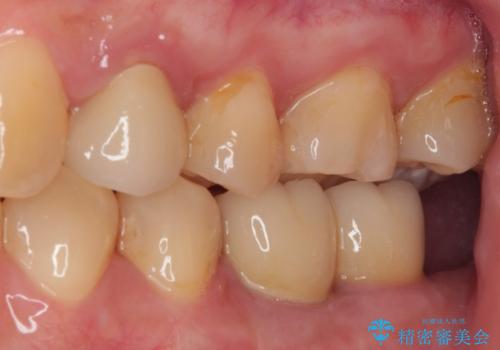

- 奥歯に問題が多くて困っているとのことで来院された患者様です。

開咬により奥歯のみが接触している状態で、前歯部にほとんど接触のない状態で、奥歯に非常に負担のかかる咬み合わせでした。

また、欠損や根管治療の必要な歯など、むし歯による問題も多く散見されました。

まずはむし歯の治療を行い、その後ワイヤー矯正にて咬み合わせを改善し、途中インプラント埋入を行い、矯正治療後に補綴治療を行うこととしました。

治療の期間と費用はかかりますが、初診時とは比べものにならないほど良好な状態にて治療を終えることができました。